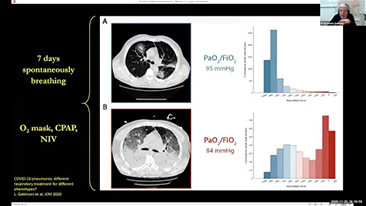

Bien dÊfinir les rÊglagesdu ventilateurpour le traitement des patients souffrant de maladies des voies respiratoires est une question très importante. Comme il incombe au mÊdecin de spÊcifier les paramètres de l'Êquipement de ventilation, ses connaissances et son expÊrience en matière de sÊlection de cesrÊglages ont un effet direct sur l'exactitude de ses dÊcisions. Le paradigme des soins de soutien aux patients a considÊrablement changÊ au cours des 20 dernières annÊes. Aujourd'hui, divers modes de ventilation et outils d'aide à la dÊcision ont ÊtÊ dÊveloppÊs autour des besoins cliniques pour aider les soignants à amÊliorer leur efficacitÊ et à Êliminer les erreurs dans les dÊcisions cliniques.